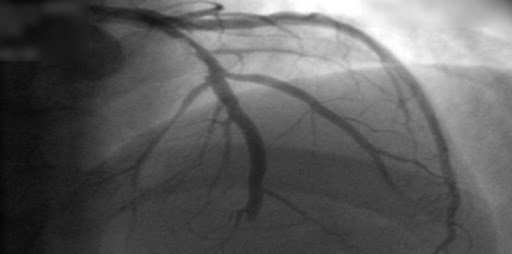

Los ensayos que demostraron el beneficio del tratamiento con betabloqueantes después de un infarto de miocardio (IM) se llevaron a cabo en una era anterior al diagnóstico moderno basado en biomarcadores y al tratamiento con intervención coronaria percutánea y una variedad de fármacos específicos. Este trabajo seleccionó pacientes con IM estudiados con angiografía coronaria temprana, con fracción de eyección del ventrículo izquierdo ≥50%, evaluando el efecto de los betabloqueantes a largo plazo, sin mostrar reducción de la mortalidad o de la recurrencia del infarto. New England Journal of Medicine, 7 de abril de 2024.